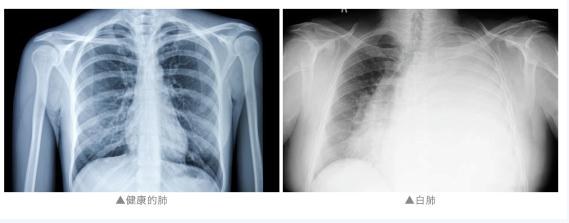

“两个肺都是白的,

发现的时候是甲流,

而且是混合感染。”

通常来说

“白肺”是指急性呼吸窘迫综合征

主要发生在重症感染时

双肺弥漫性病变进展迅速

其症状和严重程度

都与支原体肺炎不同